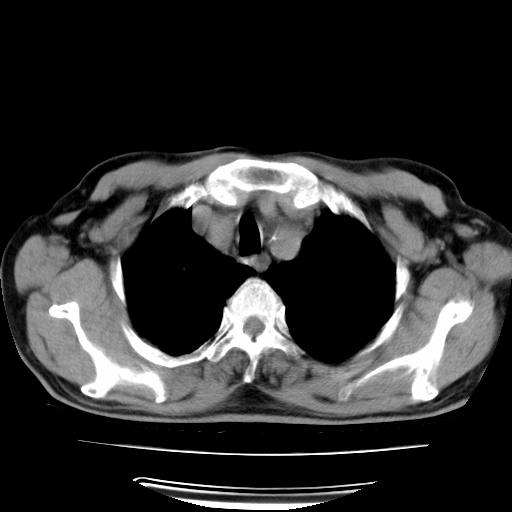

男,71岁,咳嗽,气喘10年,再发并咯血.胸片见气胸

考虑  左肺中心型肺癌伴阻塞性肺炎,肺不张,纵膈淋巴结肿大。慢支炎,肺气肿,左侧气胸肺压缩5%

左侧中央型肺癌伴纵膈淋巴结转移。

左肺中心型肺癌伴阻塞性肺炎,肺不张,纵膈淋巴结肿大

1)考虑左肺中心型肺癌伴阻塞性肺炎、左肺下叶肺不张、左侧肺气肿,纵膈淋巴结转移。2)左侧气胸(肺组织压缩约5%)。

左肺中心型肺癌伴阻塞性肺不张、肺气肿 。

1)考虑左肺中心型肺癌伴阻塞性肺炎、左肺下叶肺不张、左侧肺气肿,纵膈淋巴结转移。2)左侧气胸。